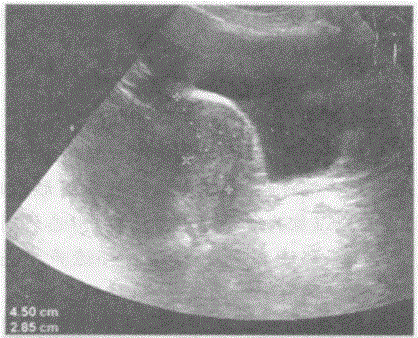

问题 临床资料:女,69岁,自诉下腹部疼痛,排便困难。 临床物理检查:右下腹可扪及一肿物,质硬,边界清,活动度好,有压痛。 超声综合描述:子宫前位,形态大小如常,肌壁回声均匀,内膜厚度0.3cm。腹、盆腔可见无回声区,上界平脐,下至耻骨联合,形态不规则,内呈网状,分隔多且厚薄不均,CDFI:分隔上可见条状血流信号,PW:呈动脉频谱,RI=0.54。

选项 A.腹盆腔多房囊性占位(卵巢癌) B.畸胎瘤 C.腹盆腔结核 D.腹盆腔包裹性积液

答案 A